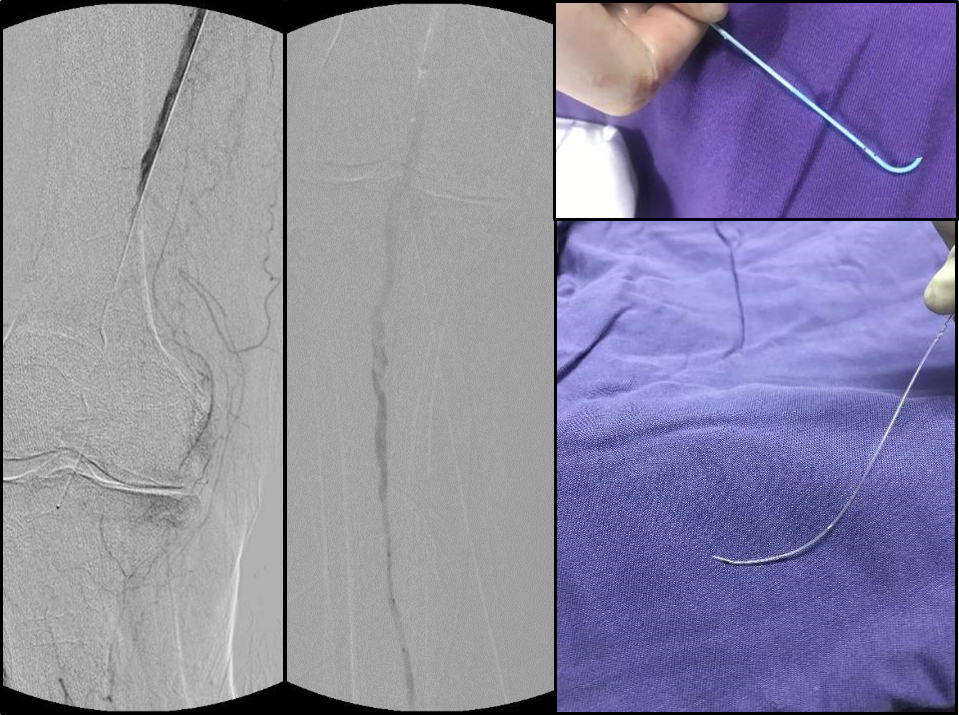

Knuckle/ADR(Antegrade Dissection and Re-entry)

AFR(Antegrade Fenestration and Re-entry)

BAM(Balloon-Assisted Microdissection)

BASE(Balloon-Assisted Subintimal Entry)

Stick-and-go

Stick-and-swap

Scratch-and-go

在操作中需遵循两大核心原则:

ALARA原则:在保证疗效的前提下,尽可能降低辐射剂量和造影剂用量。